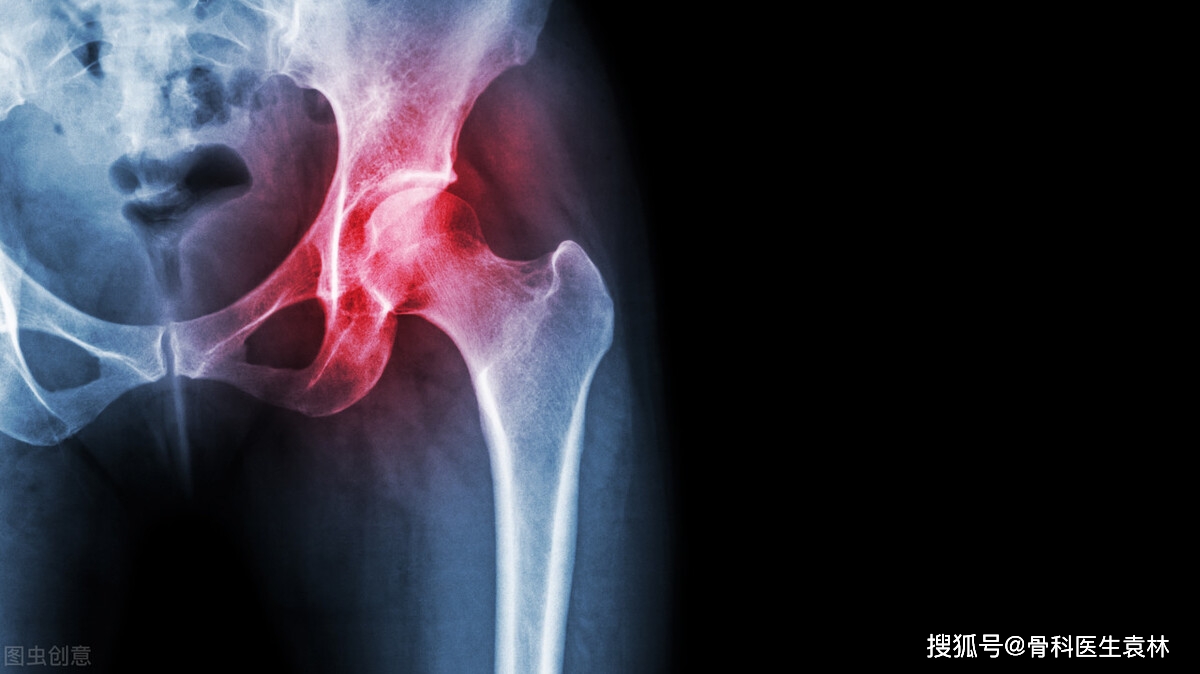

摘要:本文介紹了股骨頭壞死的早期信號及其識別。文章指出,股骨頭壞死的早期可能表現(xiàn)為髖關(guān)節(jié)疼痛、僵硬和輕度活動(dòng)受限,這些癥狀容易被忽視。通過了解這些早期信號,人們可以更好地識別并重視,從而及時(shí)進(jìn)行診斷和治療,避免病情惡化。文章強(qiáng)調(diào)早期識別的重要性,并提醒公眾關(guān)注自身健康,及時(shí)就醫(yī)。

股骨頭壞死是一種常見的骨科疾病,其早期信號往往容易被忽視,了解這些早期信號,及時(shí)診斷和治療,對于防止病情惡化至關(guān)重要,本文將詳細(xì)介紹股骨頭壞死的早期信號,并引導(dǎo)讀者關(guān)注自身健康,及時(shí)就醫(yī)。

股骨頭壞死的早期信號

1、疼痛:股骨頭壞死的最初癥狀通常是疼痛,疼痛可能出現(xiàn)在髖關(guān)節(jié)周圍,表現(xiàn)為輕度不適或隱痛,隨著病情的發(fā)展,疼痛可能逐漸加劇,并可能影響到膝關(guān)節(jié)和大腿前側(cè),需要注意的是,這種疼痛在活動(dòng)時(shí)可能加重,休息后緩解。

2、僵硬與活動(dòng)受限:關(guān)節(jié)僵硬是股骨頭壞死的另一個(gè)早期信號,患者可能會(huì)發(fā)現(xiàn)關(guān)節(jié)活動(dòng)范圍減小,如彎曲、伸展或旋轉(zhuǎn)時(shí)感到困難,這種僵硬感可能導(dǎo)致行走、站立或坐下時(shí)的不適。

3、疲勞感:許多患者在日常生活中會(huì)感到持續(xù)的疲勞,尤其是在關(guān)節(jié)活動(dòng)時(shí),這種疲勞感可能是由于關(guān)節(jié)炎癥引起的,也可能是由于肌肉和骨骼的應(yīng)激反應(yīng)導(dǎo)致的。

4、跛行:隨著病情的惡化,患者可能會(huì)出現(xiàn)跛行,這是因?yàn)樘弁磳?dǎo)致行走時(shí)的不便,進(jìn)而引發(fā)步態(tài)的改變,跛行可能會(huì)進(jìn)一步加劇關(guān)節(jié)的磨損和炎癥。

股骨頭壞死的診斷與治療

1、診斷:股骨頭壞死的診斷通常通過醫(yī)生的體檢、X光檢查、核磁共振(MRI)等方法進(jìn)行,醫(yī)生會(huì)根據(jù)患者的癥狀和體征,結(jié)合影像學(xué)檢查結(jié)果,作出準(zhǔn)確的診斷。

2、治療:股骨頭壞死的治療方法包括藥物治療、物理治療和手術(shù)治療等,早期治療通常側(cè)重于緩解疼痛、減輕炎癥和改善關(guān)節(jié)功能,在病情嚴(yán)重的情況下,可能需要手術(shù)治療以重建關(guān)節(jié)功能。

股骨頭壞死是一種嚴(yán)重的骨科疾病,早期識別和治療對于防止病情惡化至關(guān)重要,了解股骨頭壞死的早期信號,如疼痛、僵硬、疲勞感和跛行等,并關(guān)注自身健康狀況,及時(shí)就醫(yī)檢查,保持健康的生活方式、避免過度使用關(guān)節(jié)和定期檢查有助于預(yù)防股骨頭壞死,診斷和治療的方法包括藥物治療、物理治療和手術(shù)治療等,患者應(yīng)根據(jù)自身情況選擇合適的治療方法。